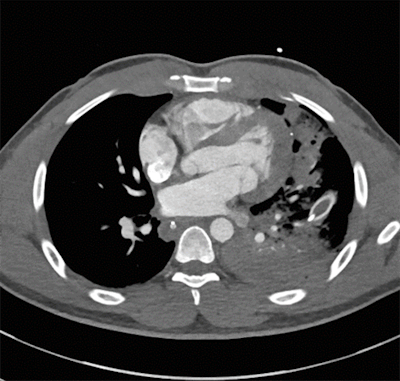

In a prior case, Nicolaou and colleagues evaluated the x-ray image of a patient who had dozens of shotgun shell fragments lodged in the chest. Though x-ray confirmed the presence of the fragments, it neither revealed the extent of damage nor helped the physicians determine the best form of treatment. To clarify the situation, they performed a CTA exam, which indicated that there was no major injury to any vessels -- ultimately confirming that it was safe to discharge the patient without invasive surgery.

CTA can offer several other advantages for diagnosis in distinct regions of the body, especially concerning the site of injury:

- Vasculature: Biphasic CTA is critical for visualizing vasculature since penetrating trauma is associated with a much higher risk of damage to the veins than blunt trauma is, he said.

- Lungs: CT is highly sensitive for pneumothorax as well as other pathology in patients with penetrating trauma that clinicians may easily miss on x-ray, such as pulmonary contusion and laceration.